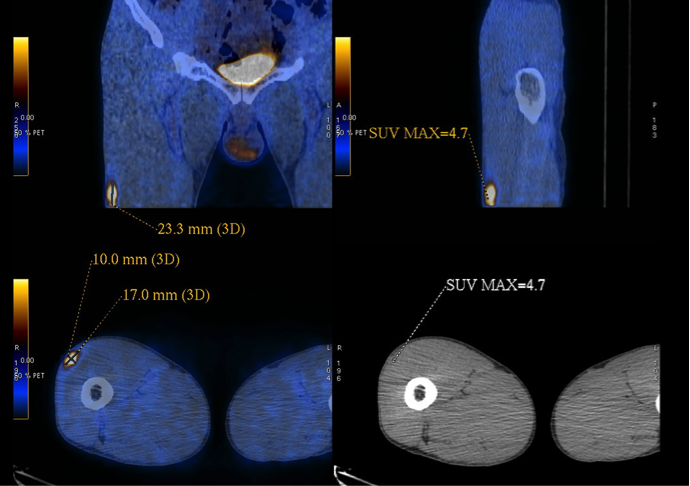

The patient was a chronic smoker (30 pack-years) and chronic drinker. He was a construction site worker and his past health was good. He presented with headache for a few weeks and was found to have signs of superior vena cava obstruction (SVCO). He did not have other complaint and the rest of the physical examination was normal. His CXR was unremarkable (Fig 4). His plain CT brain was also unremarkable. His initial blood tests including complete blood picture, renal & liver function test, erythrocyte sedimentation rate, urate, lactate dehydrogenase and tumor markers (including carcinoembryonic antigen, alpha-fetoprotein and prostate-specific antigen) were normal. His sputum was negative for culture, acid fast bacilli and cytology. His contrast CT thorax showed enlarged lymph nodes (LN) in the right lower paratracheal, pre-carinal & right hilar region and aorto-pulmonary window. The enlarged right lower paratracheal and precarinal LN compressed the brachiocephalic veins and superior vena cava (Fig 5). FOB with transbronchial needle aspiration under endobronchial ultrasound guidance (EBUS-TBNA) were done. The specimen of the right lower paratracheal LN was reported as suboptimal while the specimen from the right hilar LN was negative for any significant pathology. In view of SVCO was a potential medical emergency, we suggested surgical biopsy of the mediastinal LNs to ascertain their nature more definitively in order to guide subsequent management. He was then referred to the thoracic surgery clinic and PET-CT was done as suggested by the thoracic surgeon. The PET-CT was reported as “There were multiple enlarged hyper-metabolic mediastinal LNs (SUVmax 3.3-6.5) and the provisional diagnosis would include lymphoproliferative disease.” A hypermetabolic focus (1.7cm x 1.0cm x 2.3cm, SUVmax = 4.7) in the periphery of the right vastus lateralis muscle was also found incidentally (Fig 6A, 6B). At that juncture, the working diagnosis was SVCO due to possible lung carcinoma with LN metastases or lymphoma. The right thigh lesion could be part of the disease or something unrelated. Right anterior mediastinotomy and biopsy of the right lower paratracheal LN were done. Histology showed a piece of fibrous tissue with marked suppurative granulomatous inflammation. However, infective stains including Ziehl-Neelsen (ZN) stain were negative. His tuberculin skin test was 24mm (that was strongly positive) and his histoplasma antibody was negative. Standard anti-tuberculosis (TB) treatment was started and the signs of SVCO resolved progressively. Later, ultrasound guided FNA of his right thigh lesion showed granulomatous inflammation and one acid fast bacillus. Thus the final diagnosis was TB mediastinal lymphadenopathies causing SVCO, and right thigh TB infection. An interval CT about four months after anti-TB treatment showed the mediastinal LNs were decreased in size.

Figure 6a and 6b